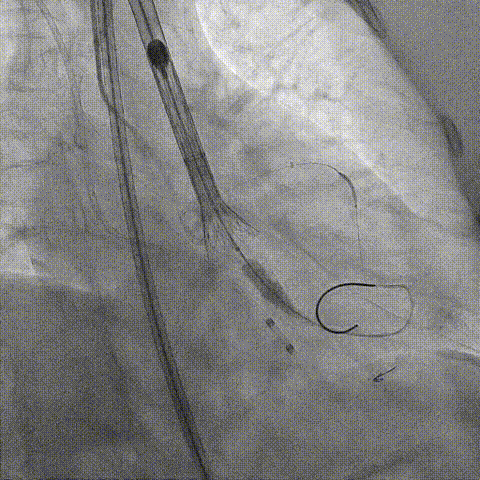

冠脉造影

Telescope™+Runthrough

18mm*40mm 预扩张

预埋 Resolute Integrity 3.5*26mm

再次评估左冠开口